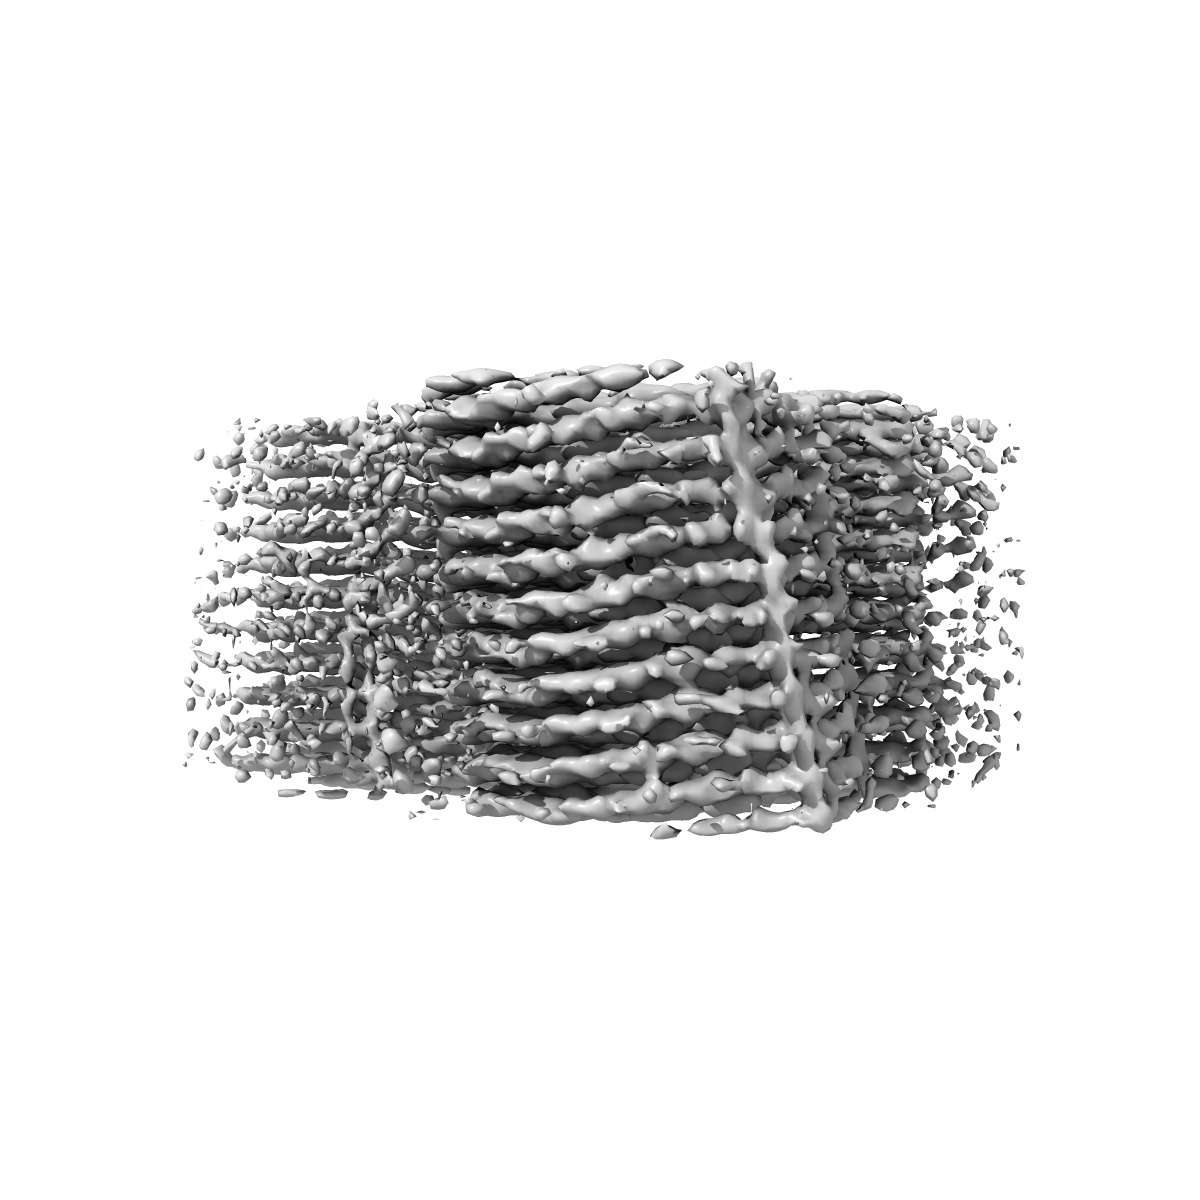

Straight Filaments purified from Down Syndrome individual brain tissue applied to graphene oxide antibody affinity grids

Cryo-EM structures reveal tau filaments from Down syndrome adopt Alzheimer's disease fold.

Ghosh U, Tse E, Yang H , Shi M, Caro CD, Wang F, Merz GE, Prusiner SB, Southworth DR, Condello C

(2024) Acta Neuropathol , 12 , 94 - 94